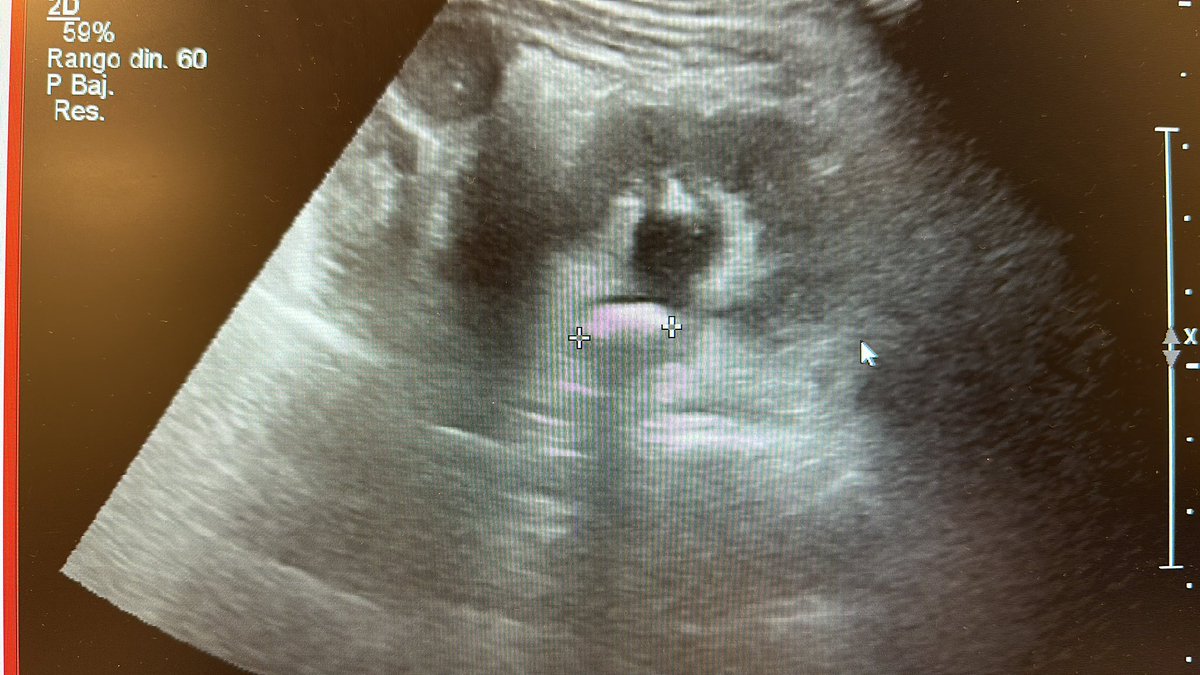

Paciente de 3 años, litiasis renal de 18x14x13 mm y litiasis ureteral.

#lupeyenchile #pedsendourology #endouroinfantil #endourologia #drreed (@pirricu)